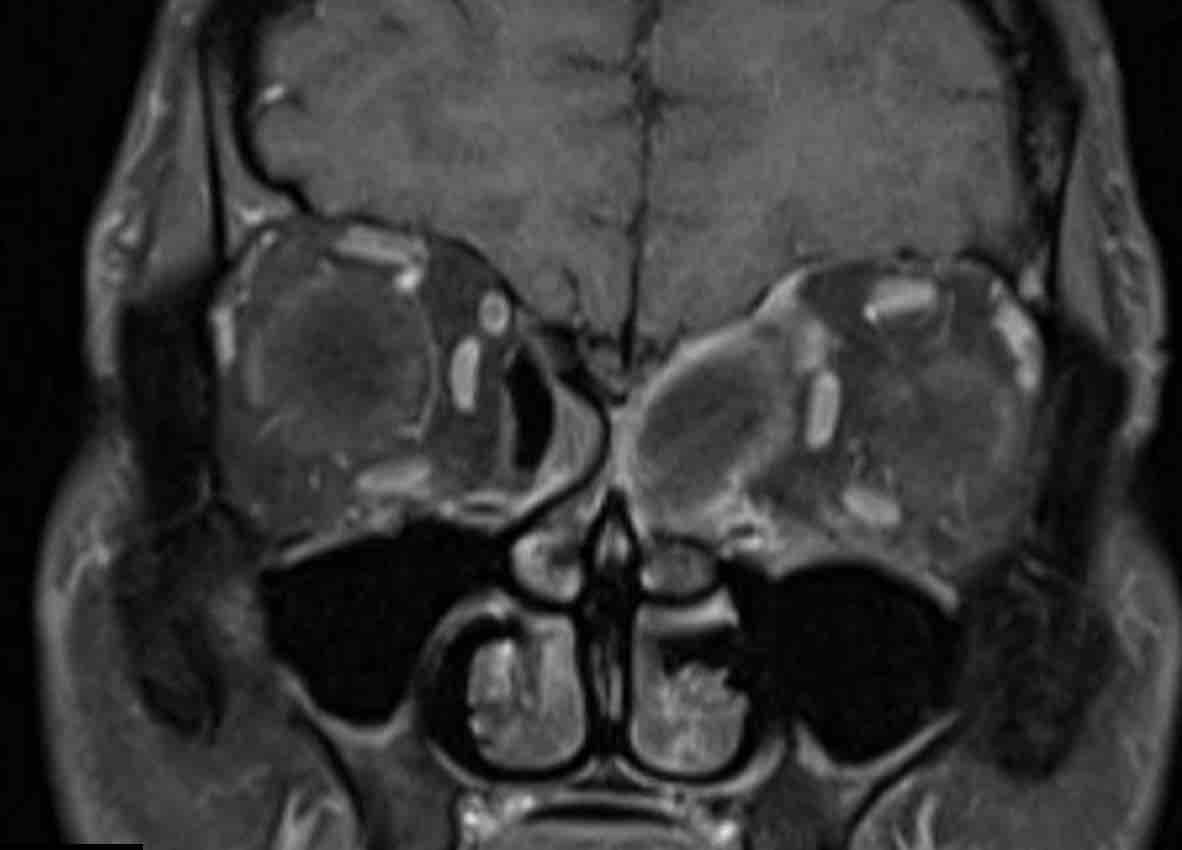

Các hình ảnh này của một bệnh nhân nam 16 tuổi với biểu hiện lồi mắt và chảy máu mũi.

Trên các hình ảnh này, có một tổn thương phá hủy xương với xâm lấn vào hốc mắt.

MRI cho thấy một khối u phá hủy một bên với hạn chế khuếch tán rõ rệt (giảm tín hiệu trên bản đồ ADC).

Như vậy, chúng ta có ba dấu hiệu cảnh báo.

Hạn chế khuếch tán là một lập luận khác chống lại chẩn đoán u xơ mạch máu vị thành niên, vì một tổn thương mạch máu sẽ không gây ra hạn chế khuếch tán.

Có xâm lấn vào hốc mắt và cả vào phần mềm phía trước của má (mũi tên).

Sinh thiết được thực hiện và cho kết quả là u cơ vân (rhabdomyosarcoma), được điều trị bằng hóa trị liệu.